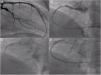

Acute thrombotic occlusion of the distal left anterior descending artery (LAD) was promptly identified (Figure 1A) and aspiration of thrombus was performed (Figure 1B and C), requiring multiple passages, followed by implantation of a 2.75 mm×18 mm Resolute Onyx drug-eluting stent (Figure 1D and E).

Left coronary artery angiography and angioplasty: (A) initial injection showing the left anterior descending coronary artery with acute thrombosis; aspirated material from the coronary territories, showing white (B) and red thrombi (C); (D) placement of a 2.75 mm×18 mm Resolute Onyx stent; (E) final angiographic result.